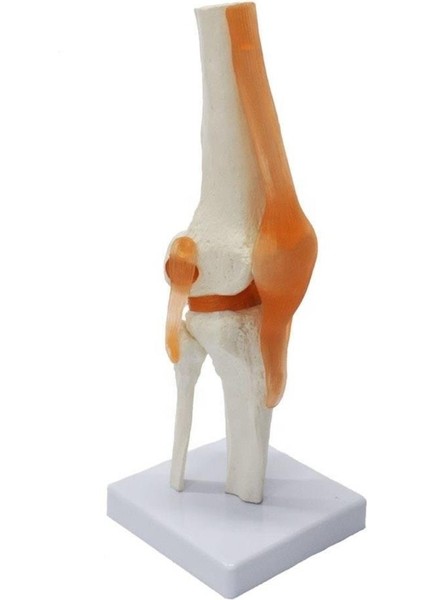

Maxi Omurga Diz Maketi Model 27

Maxi Omurga Maket Modellerimiz Pvc Materyalden Yapılmıştır. Birebir Aynı Detaylara Sahiptir. Esnek Yapıya Sahiptir. Doktorlar, Fizyoterapistler Hem Okulda Eğitim Sırasında Hemde Klinikte Kullanabilir. İster Hediye Edin İsterse De Kendiniz İçin Temin Edebilirsiniz.